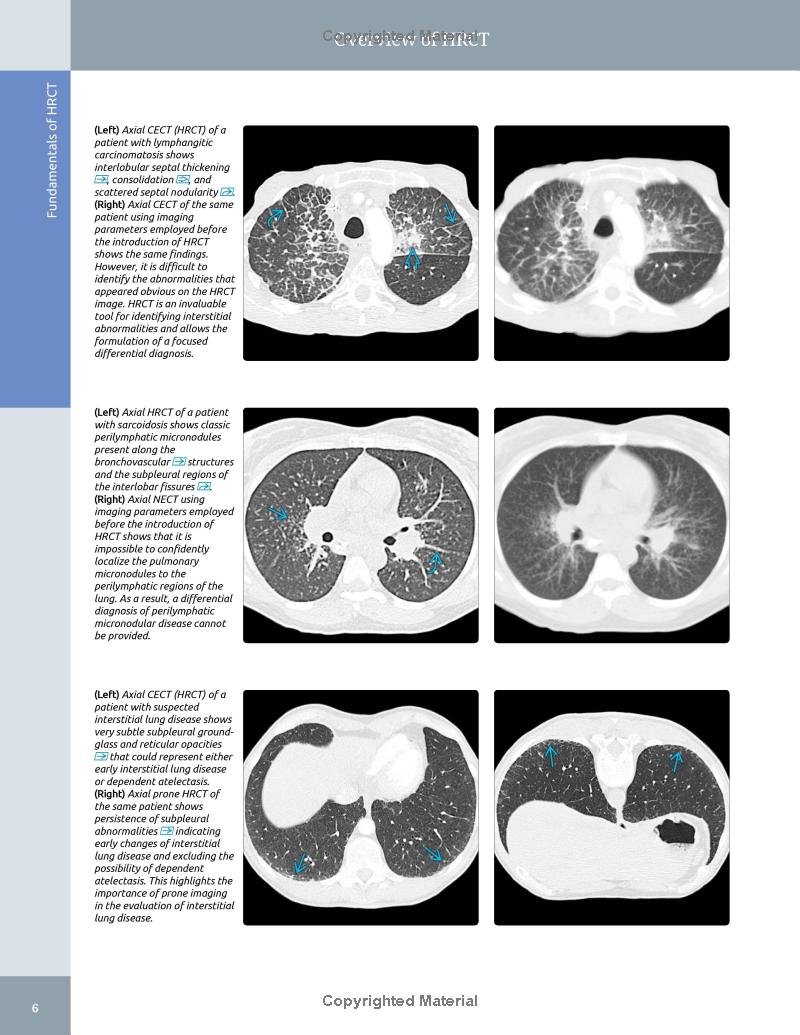

– Superb illustrations with comprehensive captions display both typical and variant findings on HRCT scans

– Introductory sections are specifically designed to lead the general radiologist to differential diagnoses from specific imaging findings, pathologic patterns, or from the disease/pathology itself